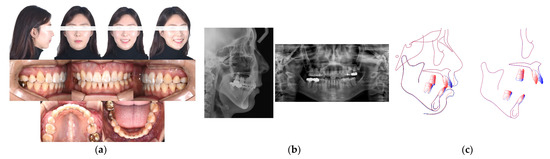

Case Report